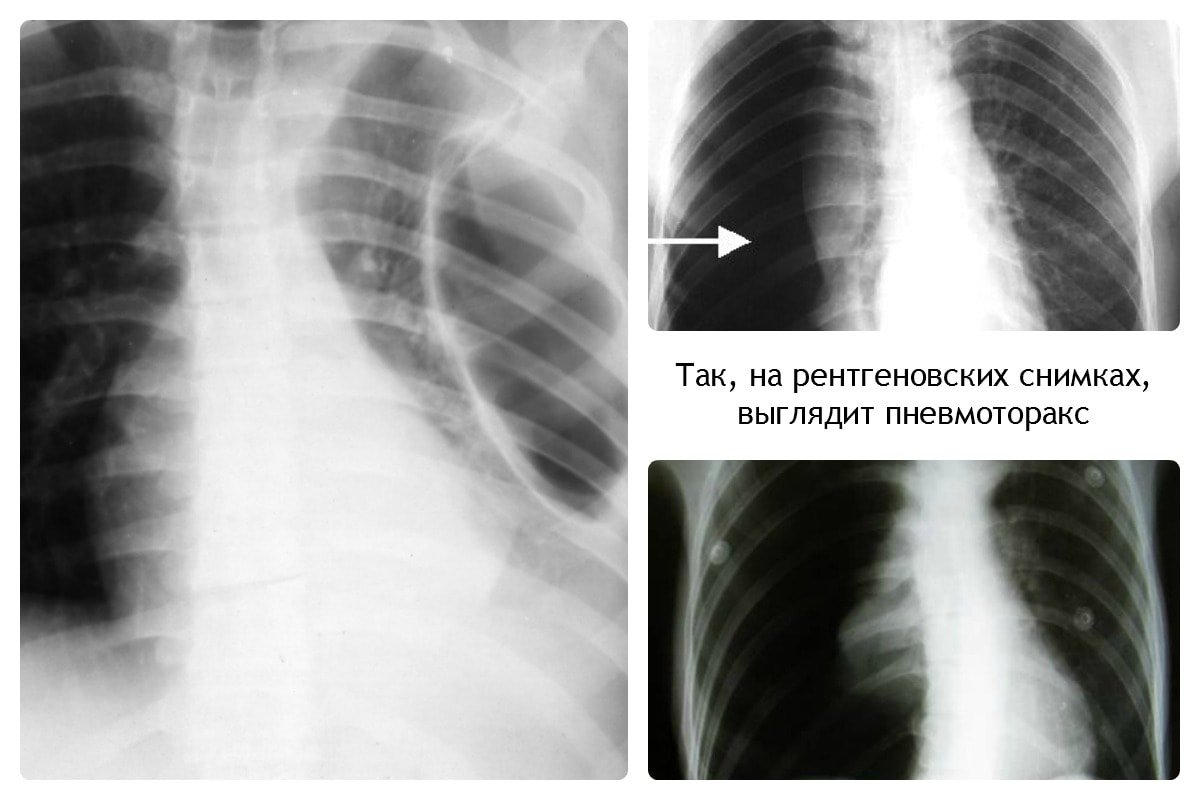

Дифференциация пневмонии от других патологий лёгких

Важным этапом постановки диагноза остаётся отличие её от других заболеваний лёгких, коронавируса. Так, при бронхите будет отсутствовать затемнение на снимке, вместо этого — усиление лёгочного рисунка.

Усиление лёгочного рисунка

В случае присутствия инородного тела, наблюдается затемнение с чёткими краями, локализующееся в нижней доле лёгкого. Спутать с воспалением типичного характера сложно.

При плеврите, на снимке скопление экссудата в поражённой области. Плеврит выступает в качестве осложнения недолеченной пневмонии.

При пневмотораксе присутствует характерный уровень жидкости. На снимке отображается как просветление, лёгочный рисунок не просматривается.

Рентгеновский снимок является основным обследованием, а в случае необходимости назначается компьютерная томография.